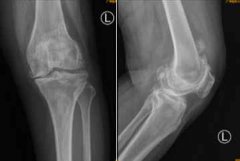

南都讯 记者李春花 通讯员 王慧 75岁的何阿姨,常年受到双膝关节疼痛的折磨,近日疼痛愈加严重,双侧膝关节逐渐弯曲变形,辗转来到广医三院关节外科...